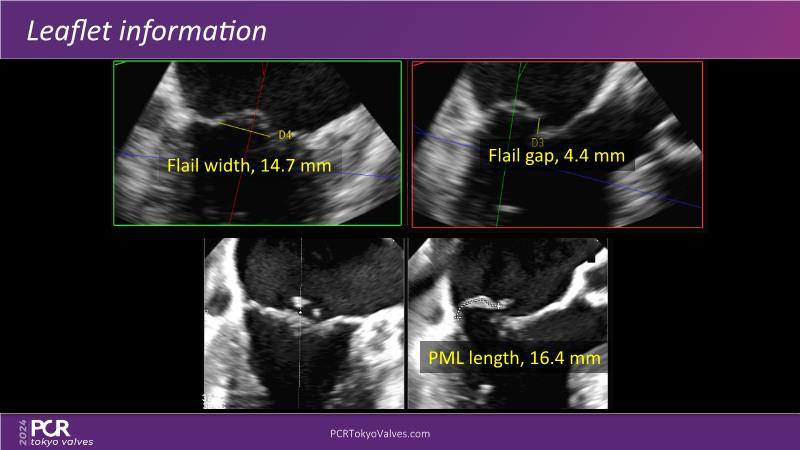

Watch this session to get an overview of a new TEER device, follow the step-by-step procedure related to initial experiences with this device for a Japanese patient with degenerative mitral regurgitation, learn about the latest data from RCT and registries, and follow discussions of challenging TEER cases!